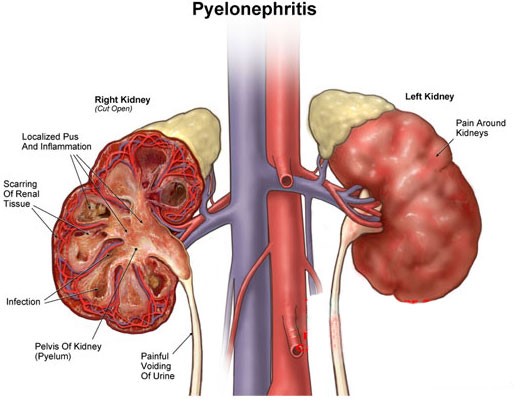

ΠΥΕΛΟΝΕΦΡΙΤΙΔΑ

Αφορά λοίμωξη των νεφρών, συμβαίνει σε άνδρες και γυναίκες με μεγαλύτερη συχνότητα στις γυναίκες λόγω της ανατομίας της ένωσης του ουρητήρα με την γυναικεία ουροδόχο κύστη. Παρουσιάζεται όταν ούρα τα οποία εμπεριέχουν μιικρόβια παλινδρομούν (ανεβαίνουν) από την ουροδόχο κύστη στα νεφρά όπου και εγκαθίστανται δημιουργώντας μια πολύ σοβαρή λοίμωξη.

Ποια τα συμπτώματα της πυελονεφρίτιδας;

- πόνο στη σύστοιχο νεφρική χώρα

- πολύ υψηλό πυρετό

- ρίγη και σπασμούς

- χαρακτηριστικό πονοκέφαλο

- εμετούς

- ναυτία

- έντονη κακουχία

Ο ασθενής έχει όψη πάσχοντος και η θεραπεία πρέπει να είναι άμεση για νη μην καταλήξει σε ουροσήψη. Χωρίζεται σε δύο κατηγορίες:

Η μη επιπλεγμένη πυελονεφρίτιδα που αφορά λοίμωξη του νεφρού με βατή την αποχετευτική μοίρα του νεφρού (τα ούρα φεύγουν ανεμπόδιστα από το νεφρό ως την ουροδόχο κύστη). Η θεραπεία αυτού του είδους αφορά αντιβιοτική και υποστηρικτική αγωγή σε σπάνιες φορές και με νοσοκομειακή νοσηλεία και είναι πιο εύκολα διαχειρίσιμη στο γενικό πληθυσμό.

Η επιπλεγμένη πυελονεφρίτιδα που αφορά λοίμωξη με εμπόδιο στην απορροή των ούρων από τα νεφρά στην ουροδόχο κύστη (από λίθο, ανατομικές στενώσεις ουρητήρα, σύνδρομα πυελοουρητικής εμβολής). Αφορούν λοιμώξεις πιο δύσκολα διαχειρίσιμες καθώς χρειάζεται παροχέτευση (ξεμπλοκάρισμα της ροής των ούρων) συνήθως χειρουργικά με τοποθέτηση ουρητηρικών καθετήρων ή νεφροστομίας σε συνδιασμό με αντιβιοτική αγωγή.

Η μη έγκαιρη διάγνωση και η σωστή θεραπεία οποιασδήποτε είδους πυελονεφρίτιδας μπορεί να οδηγήσει σε ουλές του νεφρού, σε καταστροφή του νεφρού ως και σε ουροσήψη με πολύ κακές συνέπειες.

Πως γίνεται η διάγνωση της πυελονεφρίτιδας;

Η διάγνωση γίνεται με εργαστηριακό έλεγχο με χρήση γενικής ούρων, καλλιέργειας ούρων και αντιβιογράμματος για την πιθανή ανάδειξη μικροβίων στα ούρα καθώς και τη μέτρηση των δεικτών φλεγμονής για τον υπολογισμό της βαρύτητας της λοίμωξης. Η διάγνωση γίνεται και με απεικονιστικό έλεγχο για την πιθανή ανάδειξη οιδήματος, υδρονέφρωσης καθώς και πιθανή ανάδειξη λίθου.

Η θεραπεία περιλαμβάνει συνδιασμούς πολύ υσχυρών αντιβιοτικών τα οποία συνήθως πρέπει να χορηγηθούν σε ενέσιμη μορφή και ανάλογα με τη βαρύτητα της λοίμωξης και την κατάσταση του ασθενούς υπάρχουν μεγάλες πιθανότητες να χρειαστεί νοσηλεία. Σε συγκεκριμένο διάστημα μετά την ανάρρωση επαναλαμβάνονται οι εργαστηριακές εξετάσεις καθώς και ο απεικονιστικός έλεγχος για αποκλεισμό μόνιμων βλαβών των νεφρών.